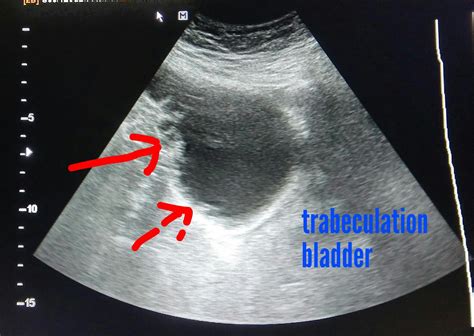

The bladder wall is principally composed of a suave muscleman called the detrusor muscleman. In a healthy state, this muscle is thin, permit the vesica to dilate well. When urinary vesica wall thickening is noted on an sonography, CT scan, or MRI, it is seldom a chief diagnosis itself; rather, it is a clinical mark or symptom that something is forcing the bladder to adjust. Think of it like a bicep muscle that have large from lifting weights; the bladder paries thickens because it is frequently compress against opposition or dealing with chronic irritation.

The thickness of the vesica wall can be measured during tomography. Generally, a mensuration of more than 3 to 5 millimeters when the vesica is empty, or more than 2 to 3 millimeter when the bladder is full, may be deal thickened. Nevertheless, these doorway are not absolute, and a physician must interpret these figure in the context of your overall health and symptoms.

- Imaging Work: Ultrasound is normally the inaugural footstep. CT scans or MRIs may cater more detailed prospect if crab or structural abnormalcy are suspected.